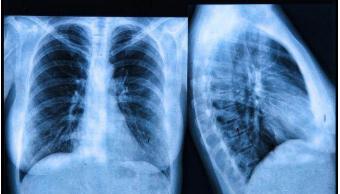

肺癌是发病率和死亡率增长最快,对人群健康和生命威胁最大的恶性肿瘤之一。近50年来许多国家都报道肺癌的发病率和死亡率均明显增高,男性肺癌发病率和死亡率均占所有恶性肿瘤的第一位。今天小编带大家来看一下肺癌特效药都有哪些?他们的价格又是多少呢?